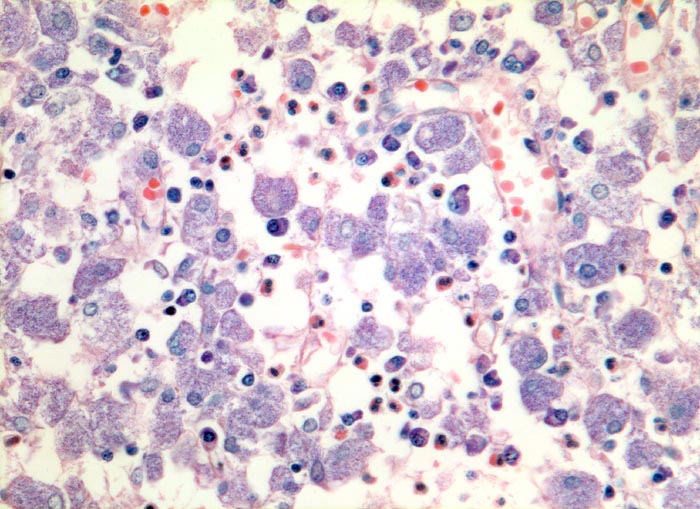

atypische Mykobakteriose (Mycobacterium avium intracellulare)

Entzündung infektiös

Lymphknoten, Kopf-cervikal

Grossleibige histiozytäre Zellen mit fein granuliertem Zytoplasma. Daneben wenig Plasmazellen und Granulozyten.

Ziehl-Neelsen Färbung: die Histiozyten sind voll von säurefesten Stäbchen.

Seit 3 Jahren HIV positiv.

Das Bild der mykobakteriellen Histiozytose wird vor allem durch atypische Mykobakterien verursacht, vereinzelt aber auch durch Mykobakterium tuberculosis.

320